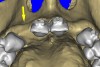

Periapical radiographs were taken to help determine the mesial-distal inclinations of the adjacent tooth roots (Figure 1). The radiographs revealed a serious issue, convergent roots for the right canine and right central, which eliminated that area as a potential implant-receptor site. The space between the left central and canine teeth was minimal, although the roots were relatively parallel. Clinical examination (manual palpation of the root eminences superiorly to the vestibule on the right side) confirmed the root convergence (Figure 2A). The flat, wide zone of the keratinized tissue and lack of interdental papilla was evident for the missing right lateral incisor. There was a marked difference in clinical appearance for the left lateral, which could impact the eventual plan of treatment (Figure 2B). Other significant clinical findings included bilateral facial bone concavities, which existed as a result of the congenitally missing tooth roots. As a diagnostic cue to the underlying bone topography, it is important to follow the demarcation between attached and unattached gingival tissue, and note the crestal width of the available keratinized tissue (Figure 2C).

Figure 4a  CT scan data was input into the treatment-planning software, which allowed (A) placement of a simulated implant and (B) the determination of the “zone” for proper placement.

Figure 4a

Figure 4b  CT scan data was input into the treatment-planning software, which allowed (A) placement of a simulated implant and (B) the determination of the “zone” for proper placement.

Figure 4b